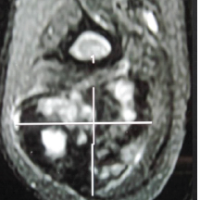

Seventeenyears ago, a45-year-old lady was admitted to our hospital due to coxarthrosis secondary to developmental hip dysplasia. In six months interval, she underwent bilateral THA with Exeter™ Universal Hip system. She had re-operated on her 3rd year because of right femoral stem fracture.Since then, she has beenexamined at the outpatient clinic regularly on1-year-based intervals. Onher last follow-up, the physical examination revealed minimal pain on her right thigh and nothing more. The patient was 1.62 m tall and weighed 84 kg, with abody mass index (BMI) of 31.25kg/m2 (obese class).There was no difference between the range of motion of bilateral knees and hips when compared withprevious records. The patient’s gait was observed adequately, and nothing significant was detected. There was no trauma or obvious activity experienced. Radiographs of the pelvis and bilateral femur were obtained,and it was demonstrated that both femoral stems were broken (Fig. 1). It was also revealed that radiolucent lines had seen both femoral stems and left acetabulum.The patient was informed of the fact that this asymptomatic situation requires revision surgery. With the informed consent of the patient, revision surgery was scheduled. Both thefractured stems were removed by extended femoral osteotomy via a lateral approach.Intraoperative examination revealed that the right acetabular component was well-fixed but there was a loosening of the left acetabularcomponent.Acetabularrevision was performed to the left side. Echelon cementless revision hip system (Smith and Nephew) was used for the right and left sides (Fig. 2). Patient was stood–up on the first post-operative day and weight – bearing was permitted as much as tolerated. . At the end of 6 weeks, full weight bearing was permitted. She returned to her routine daily life activities after 4 months. The preoperative Harris score was 90.25, and the postoperative Harris score was 91.25. After 2-year follow-up, no major or minor complications were reported.